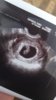

Mun ei pitänyt mennä varhaisultraan, mutta nyt on pakko. Reissussa alkoi verinen vuoto. Olin kyllä vaeltanut pitkästi, että voiskohan fyysinen rasitus tehä. Mutta ois vielä ulkomaille lähtö tällä viikolla, niin pakko raskia maksaa se 200€ mielenrauhasta. Huomenna selviää. Pitkä yö ja päivä edessä.